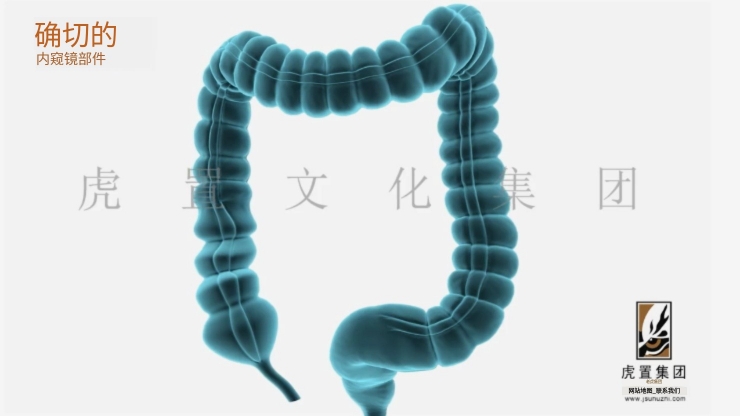

深耕于数字设计及展示领域的虎置文化集团正努力成为全球知名的数字设计及展示服务商,创办至今20年,旗下五家子公司,是集设计、展示、施工于一体的综合运营服务商。集团旗下控股上海虎置文化集团有限公司、江苏虎置文化传播有限公司、上海比筑视觉艺术设计有限公司、上海虎置建筑设计有限公司和江苏艺派数字科技有限公司四家子公司,为不同行业客户提供基于文化创意服务的整体解决方案。

致力于:全案设计、展馆展厅、三维动画、卡通动漫、影视广告、3D效果图等综合服务,设计包括:建筑设计、景观设计、规划设计、展馆设计、室内设计、 BIM设计;展示包括:三维动画、全息展示、影视广告、数字展馆、二维动漫、3D仿真效果图、VR&AR等;施工包括:展馆展厅、室内装饰、幕墙工程、亮化工程。